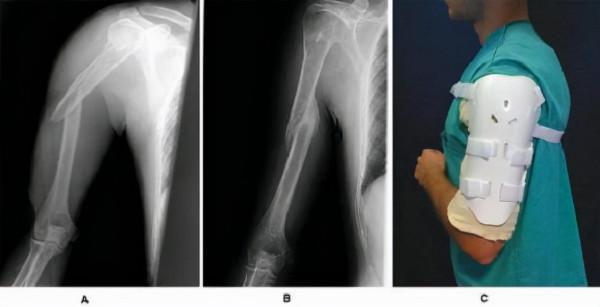

肱骨即上臂骨,其上端透過肱骨頭與肩關節相連,下端透過肱骨髁與肘關節相連。所謂肱骨幹骨折,是指肱骨頭和肱骨髁以外的肱骨主幹部分骨折。

根據骨折型別的不同,可將肱骨幹骨折分為橫形骨折、斜行骨折、螺旋形骨折和粉碎型骨折等型別,如果是不穩定的橫形骨折和粉碎型骨折,或者伴有重要神經和血管損傷(肱骨上附有諸多肌肉,骨折後常常因為肌肉張力使骨折移位、成角增大,使貼近肱骨的血管和神經受損),就必須要採用切開、復位、固定、修復的手段進行手術治療,並在術後參考如下方案進行康復治療。